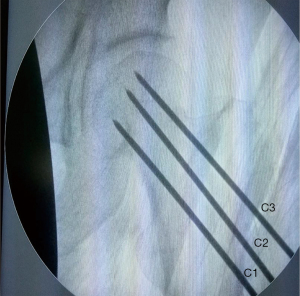

The localization method of the upper two guide pin insertion points

The upper two guide pins should be implanted after the successful implantation of the lower guide pin. They were located on horizontal line L4, with a vertical distance to L3 of approximately 1 cm. The horizontal distance between the two insertion points marked as C2 and C3 was approximately 1 cm (Figure 1B). As with the lower guide pin, the thickness of soft tissue should also be considered when determining the guide pin insertion points on the skin. Additionally, the guide pins were placed close to the posteroposterior cortical bone and the superoanterior cortical bone of the femoral neck. The three guide pins were placed evenly in an inverted triangle configuration in the femoral neck.

The patient was a 63-year-old male worker, previously fit and well, who fell and hurt himself by accident. He felt severe pain in his left hip and was sent to Affiliated Hospital of Shandong University of Traditional Chinese Medicine immediately. We found external rotation deformity of his left limb and performed an X-ray examination. Unfortunately, we found a left femoral neck fracture (Garden Index III) (Figure 2). Due to the significant displacement, the patient was treated surgically with closed reduction and percutaneous internal fixation using three parallel cannulated screws placed in an inverted triangle configuration. The three guide pins were inserted (Figure 3) into the three guide pin insertion points (C1, C2, and C3) that had been located with our localization method (Figure 4). Then three parallel cannulated screws were implanted to fix the fracture (Figure 5). Postoperative follow-up was performed periodically over 12 months to evaluate the hip function and observe complications. Overall, we achieved a satisfactory therapeutic outcome without complications (Figure 6).